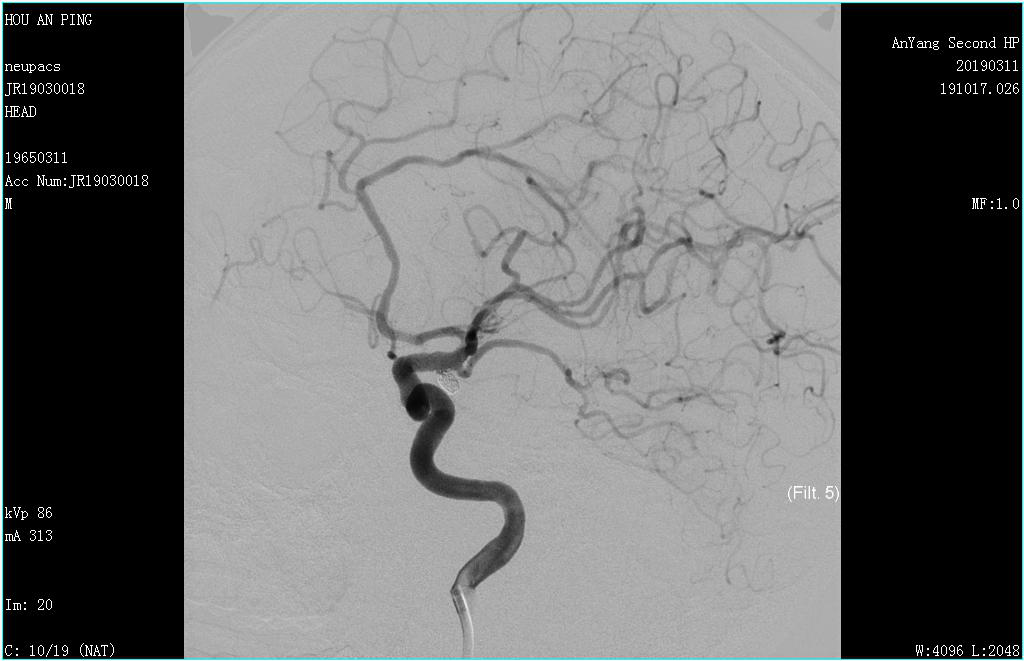

此時(shí),時(shí)間為上午10時(shí),安排好患者,陳醫師緊急報告科室主任王喜芹及副主任文海杰,并聯(lián)系介入科,開(kāi)展多學(xué)科聯(lián)合救治模式。兩位主任及時(shí)趕到醫院,然而介入科李恩醫師及楊芳護士均在外地,但是,面對著(zhù)隨時(shí)再次破裂的動(dòng)脈瘤及病情的危急,他們兩位接到電話(huà)后二話(huà)沒(méi)說(shuō),以最快的速度返回醫院。同時(shí)醫院這邊進(jìn)行著(zhù)有條不紊的術(shù)前準備。很快,多方人員已集結至導管室,下午17:00患者被推入導管室,行腦血管造影術(shù)。造影可見(jiàn)左側后交通動(dòng)脈有一動(dòng)脈瘤,大小約2.6mm×3.6mm,形態(tài)不規則??吹絼?dòng)脈瘤在屏幕上顯影,醫護人員松了一口氣,病變部位找到了,但同時(shí)心情更緊張了,因為接下來(lái)要打一場(chǎng)艱難的硬仗。

團隊人員及時(shí)將造影結果與患者家屬溝通,建議行顱內動(dòng)脈瘤栓塞術(shù),家屬商量后再決定。然而時(shí)間不等人,病情不能耽誤,每增加一秒病人就需承受動(dòng)脈瘤破裂的巨大風(fēng)險,在家屬商量的同時(shí)陳醫師迅速聯(lián)系上級醫院專(zhuān)家,專(zhuān)家組明確了腦血管動(dòng)脈瘤栓塞的治療計劃。當患者家屬商量后同意治療方案時(shí),我們的神經(jīng)內科介入團隊已與專(zhuān)家組確定了治療方案和治療時(shí)間,在醫療科協(xié)調指揮下,多學(xué)科協(xié)作,麻醉科、器械科都及時(shí)到位。次日17:30,專(zhuān)家到達,再次造影后于全麻下行主動(dòng)脈弓+全腦血管造影術(shù)+經(jīng)股動(dòng)脈支架輔助下顱內動(dòng)脈瘤栓塞術(shù)。導絲在路途指引下小心置于動(dòng)脈瘤瘤腔內,經(jīng)微導管依次填入彈簧圈,1個(gè)、2個(gè)、3個(gè)...,填入第8個(gè)彈簧圈時(shí)釋放困難,病人瘤頸寬,擬行支架輔助下動(dòng)脈瘤栓塞,將支架準確釋放于動(dòng)脈瘤瘤頸處,釋放最后一個(gè)彈簧圈,填塞過(guò)程順利,造影顯示瘤腔栓塞致密,動(dòng)脈瘤瘤腔未見(jiàn)造影劑顯影,載瘤動(dòng)脈前向血流良好,手術(shù)過(guò)程順利,家屬長(cháng)松了一口氣,為表達感激之情,特意給陳醫師及文主任包了兩個(gè)2000元的紅包,兩位醫師婉拒,并及時(shí)制定下一步治療方案,因為這場(chǎng)仗,還沒(méi)到吹響勝利號角的時(shí)候。接下來(lái)病人要面臨吸收熱、癲癇、腦血管痙攣、下肢靜脈血栓等風(fēng)險。